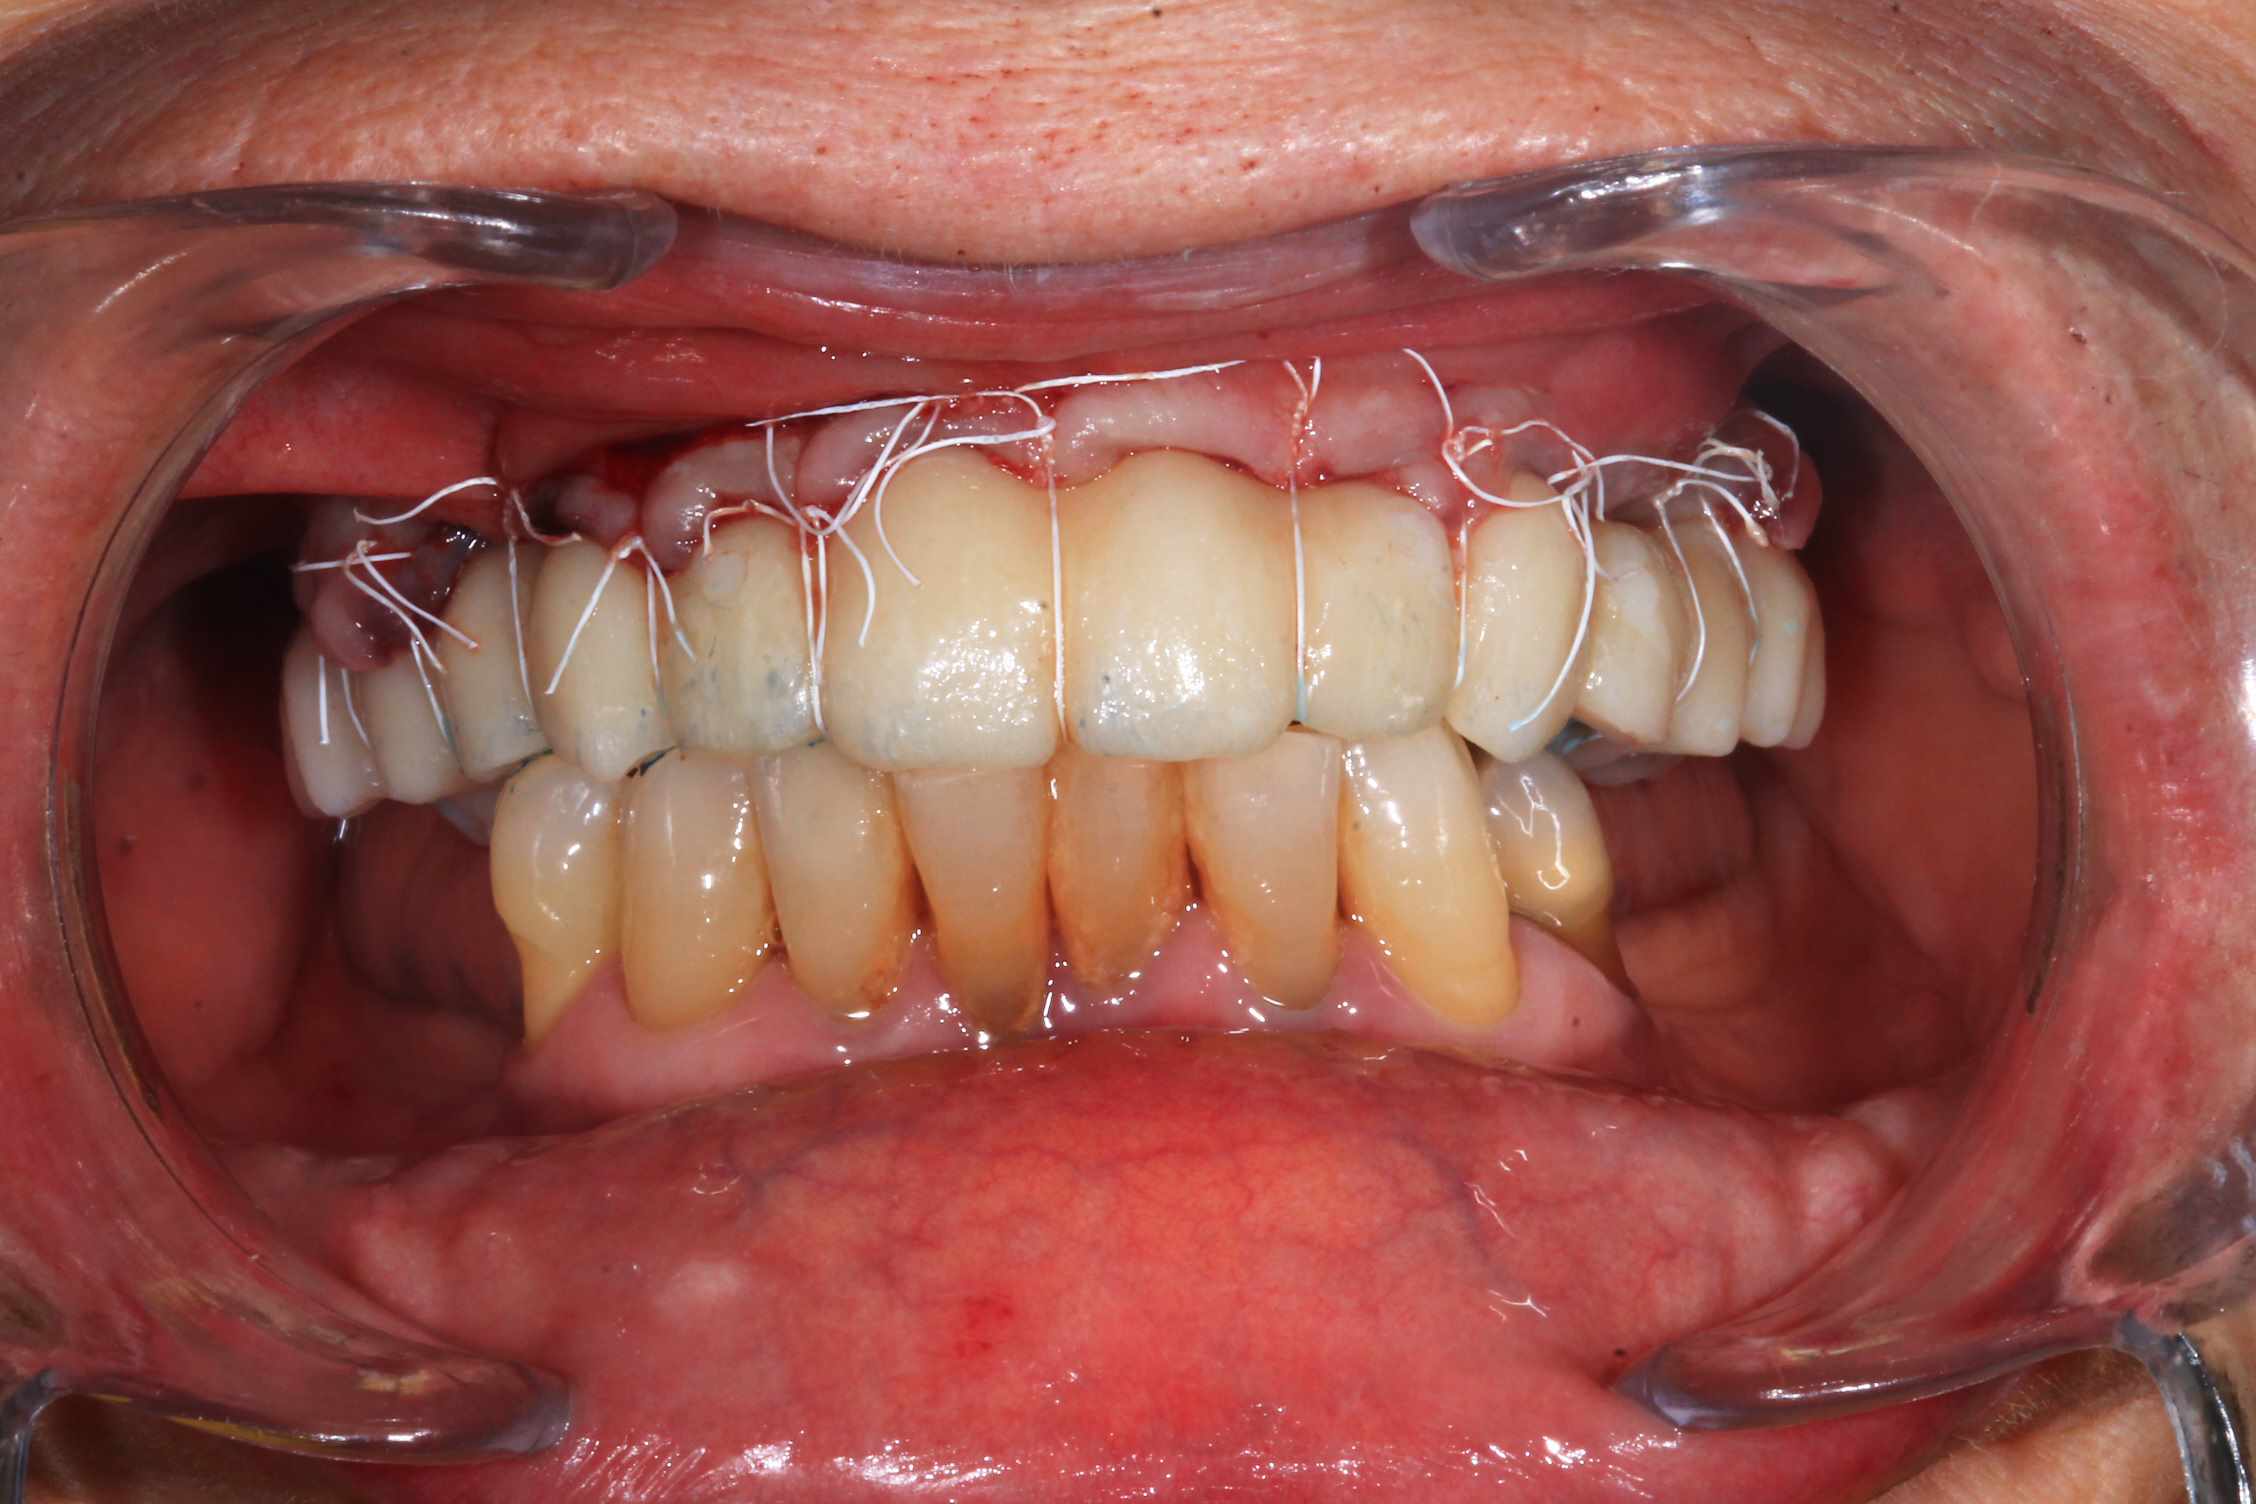

Cas 2 , suite : avec une saussage au passage..

le patient arrive a 9 h, Prise de sang, PRF, injection de corticoïde, anesthésie et installation au bloc. Premier coup de bistouri a 9h30. Dernière suture a 11h30.

Chir : extraction, implant flapless et pose du bridge imprimé Flexera rosenscrew.